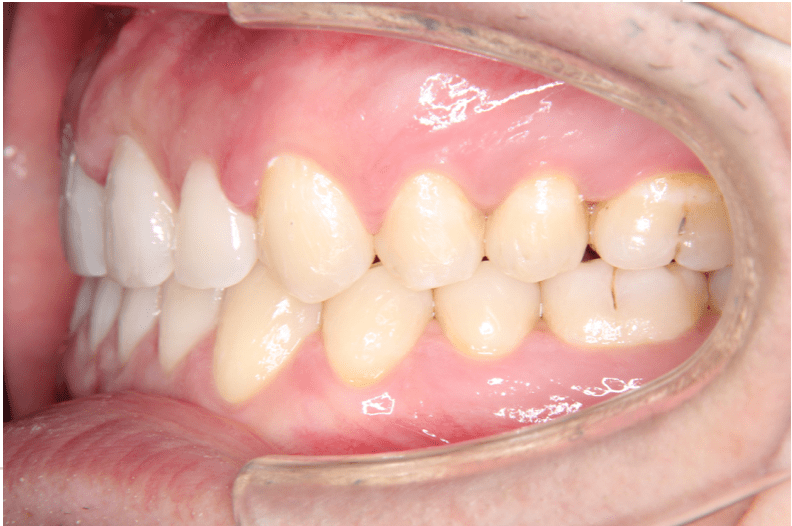

治療後(右)

上下開いていた症例ですので、下を閉じてから上を閉じる計画を立てました。

症例情報:

【患者】 20代男性

【主訴】 前歯のすき間がきになる。

【診断】 空隙歯列

【抜歯の有無】 非抜歯

【治療期間】2年0ヶ月 通院回数15回

【治療内容】親知らずを抜歯した後、マウスピース型カスタムメイド矯正歯科装置(製品名インビザライン 完成物薬機法対象外)を使用して主訴である叢生の改善を行いました。

【費用】88万(税込)